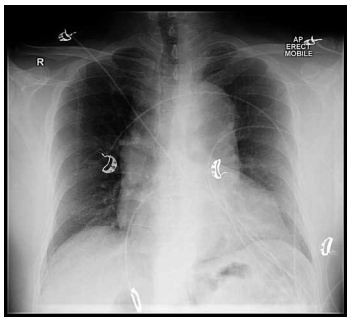

Homem, 62 anos, hipertenso e portador de DPOC leve, chega ao pronto-socorro com palpitações intensas, iniciadas há cerca de 40 minutos, associadas a leve dispneia. Ao exame:

PA 104 × 62 mmHg; FC 188 bpm; FR 22 irpm; saturação 95% AA. Está consciente, sudorético, sem dor torácica. Realizou o ECG a seguir:

Foi realizada manobra vagal: sem resposta significativa. Na sequência, foram administradas 6 mg de adenosina, ocorrendo breve pausa e retorno imediato da taquicardia, mantendo o mesmo padrão. Eco portátil: função normal, sem sinais de congestão.

Qual é a conduta mais apropriada nesse cenário?